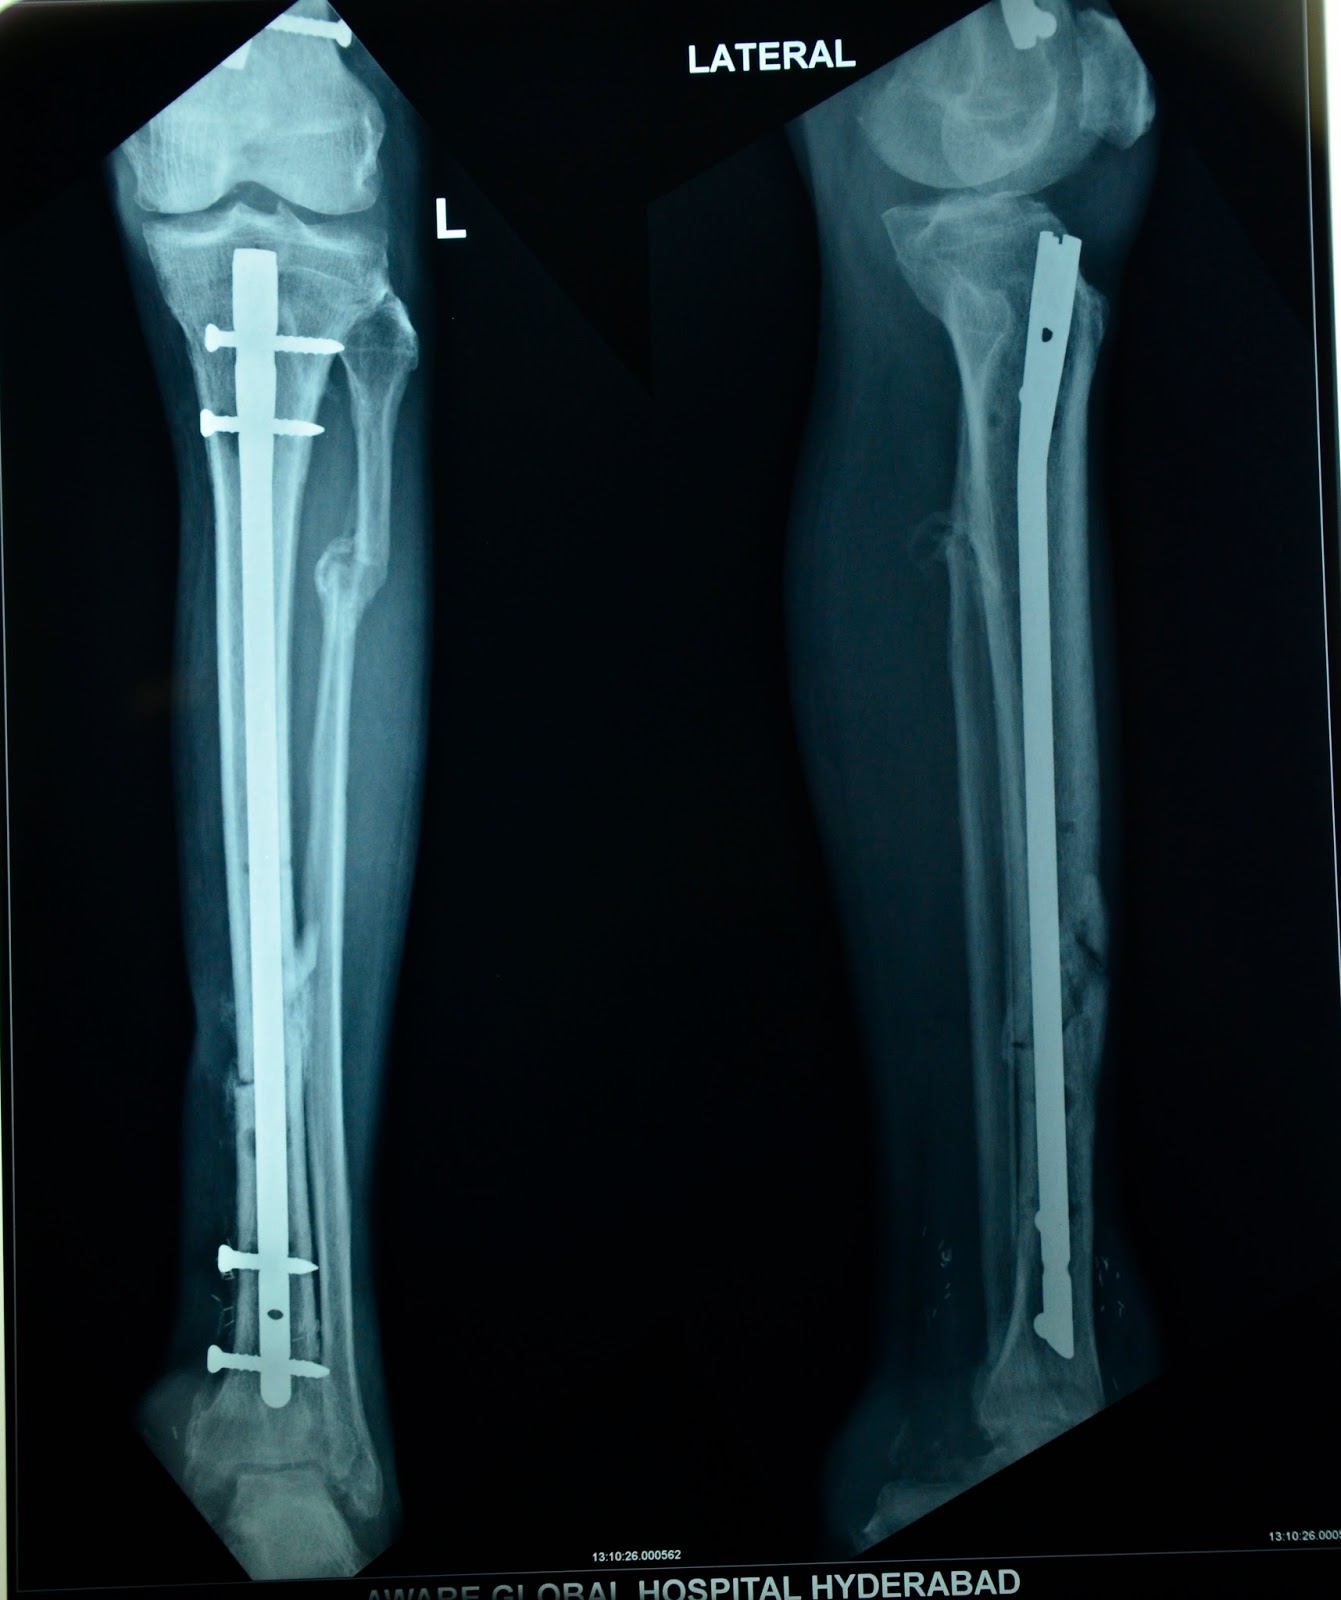

Ankle repair surgery hires stock photography and images Alamy Crush Injury Ankle Crush injuries of the foot are serious and can be difficult to manage. A crush injury occurs when force or pressure is put on a body part. Severe crush injury increases the risk for organ failure and death due to the possible development of crush syndrome, which is the. A foot crush injury may take from a few days. In. Crush Injury Ankle.